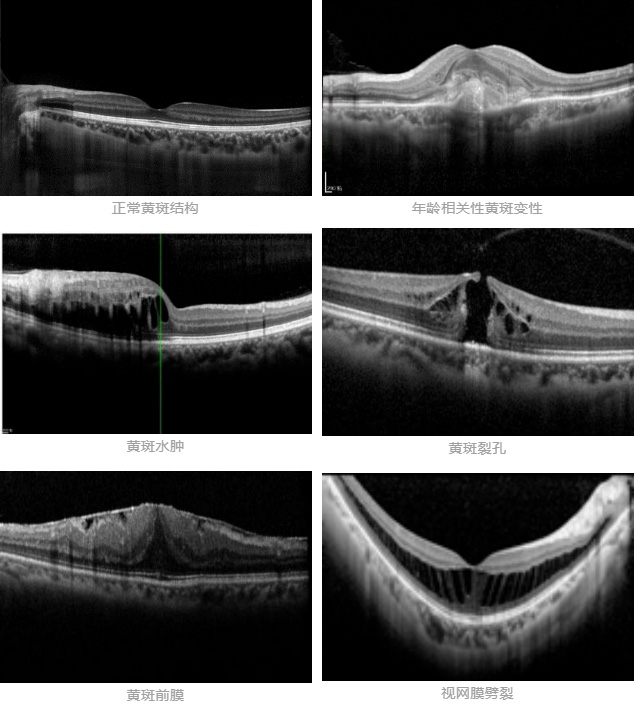

眼科OCT更多用于眼底黄斑疾病的检查(如年龄相关性黄斑变性、黄斑水肿、黄斑裂孔、黄斑前膜、视网膜劈裂等),设备发出的光线经瞳孔射入后聚焦于黄斑部位,其对于眼底结构的扫描深度仅为2mm,扫描宽度可在3-10mm范围内进行调节。对于超出上述扫描范围的组织结构,OCT设备就会存在一些局限性了。